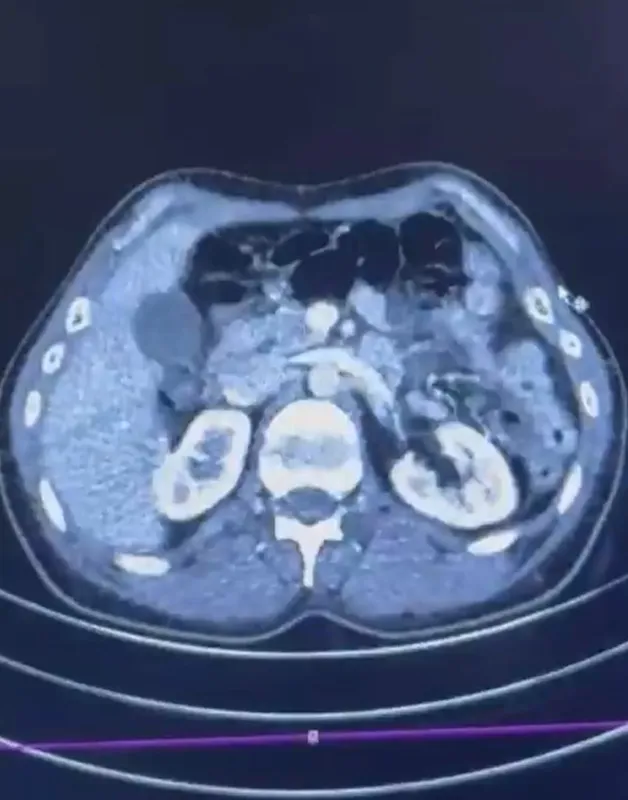

Edinilen bilgiye göre Narkotik Suçlarla Mücadele Şube Müdürlüğü ekiplerince uluslararası uyuşturucu madde ticareti yapan kurye şahıslara yönelik gerçekleştirilen çalışmalarda, İran’dan Türkiye’ye uyuşturucu madde getirdiği tespit edilen şüpheli şahısların yakalanması amacıyla operasyon düzenlendi. Düzenlenen operasyonda; S.C., R.B.C. ve G.M. yakalandı. S.C. ve R.B.C.’nin Kayseri Şehir Hastanesi’nde yapılan iç beden muayenelerinde, mide kısımlarında bulunduğu tespit edilen 50 adet kapsül şeklinde toplam 554 gram uyuşturucu madde ele geçirildi. Şüpheliler gözaltına alınarak haklarında ’Uyuşturucu Madde Ticareti Yapmak’ işlem başlatıldı.